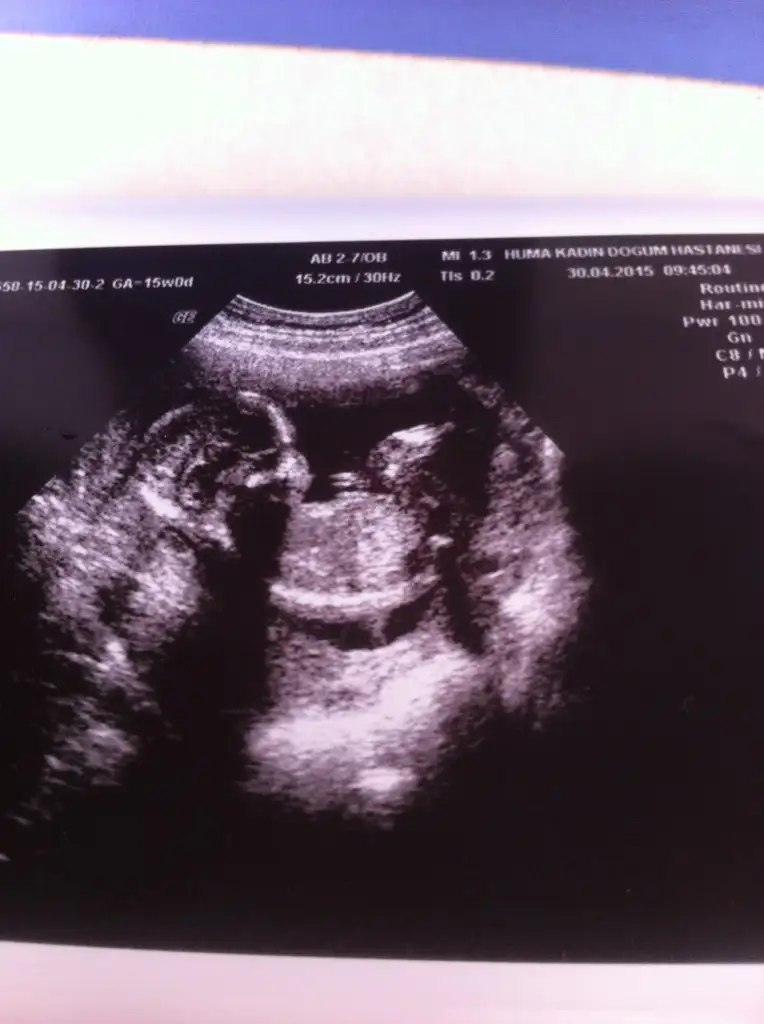

dr soylemeden siz gorun genital nub teorisi ( bebegin cinsiyeti)

20150506_145252.webp 20150506_145231.webp Arkadaşlar benim kuzuma da bakar mısınız? Resimleri ters yuklemişim düzeltemedim kusura bakmayın.12+5 teyiz

Eklentiler

• 20150506_145252.webp

20150506_145252.webp

12,3 KB · Görüntüleme: 164

• 20150506_145134.webp

20150506_145134.webp

10,4 KB · Görüntüleme: 169